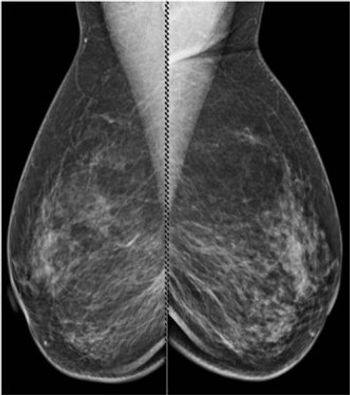

A 57-year-old patient presents for evaluation of right nipple discomfort. The patient has family history of a mother and sister with premenopausal breast cancer.